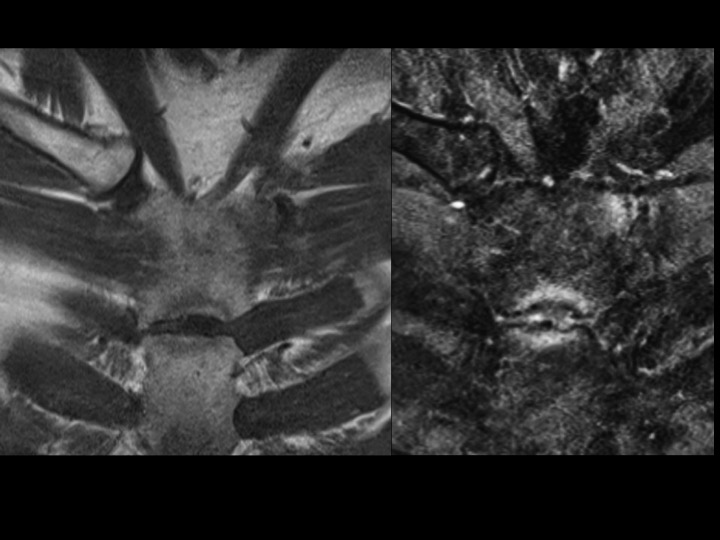

39M left medial clavicle pain with 5 yrs intermittent multifocal pain

The referrer ordered MRI of each clavicle, but the left side included the manubrium and upper sternum as well at the medial right clavicle. Symptoms are only near the left sternoclavicular joint. There are bilateral bright foci in the articular cartilage of the medial clavicle (white arrows), with subtle subchondral erosion but no BME on the left. There is left sided subchondral edema at the costomanubrial junction (yellow arrows). Obvious erosion with edema at the manubriosternal articulation The referrer did not notice any rash, though it sounds like he didnt think to look. Im thinking SAPHO and seronegative spondyloarthropathies; agree or not? The orthopedist says he will refer him to rheumatologist and will get me follow up when available. Reference article.